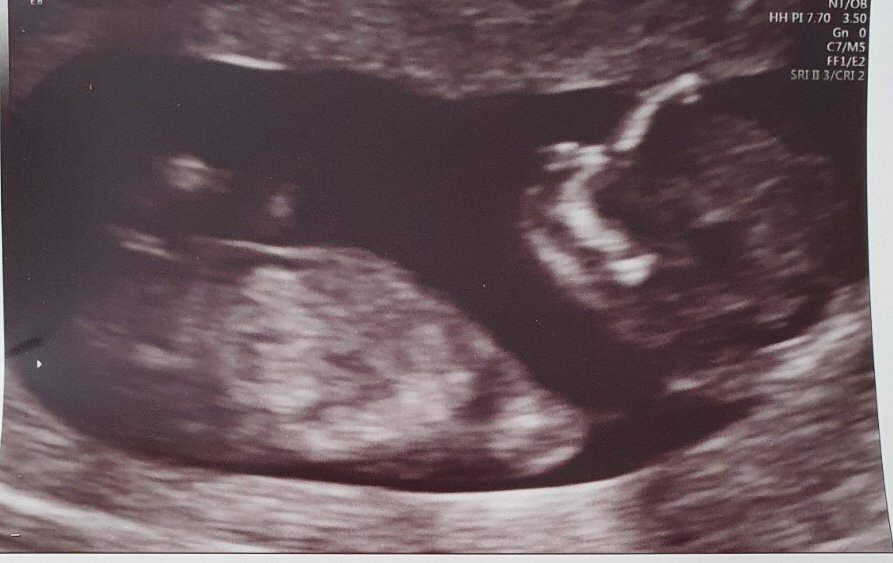

On 27 January, I had a frozen embryo transfer and on 6 February those two little pink lines appeared. My six, nine and 12-week scans showed a healthy baby. However, it was short-lived. In April, at the height of the pandemic, an 18-week scan showed our baby had severe PUV; a blocked bladder, which would prevent his kidneys, lungs and heart from developing. We had no choice but to terminate for medical reasons (TFMR).